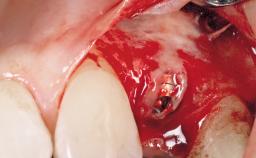

Late Flapless Placement of an Implant in a Maxillary Left Central Incisor Site

A 39-year-old male patient presented with a chief complaint of discomfort and gingival discoloration around his maxillary left central incisor. He was in good general health and was a non-smoker. His past dental history was significant because of the traumatic fracture of tooth 21 in a sporting accident at age 13. Initial dental treatment included endodontic therapy and a full-coverage restoration. The patient became symptomatic 5 years later, when structural failure of the tooth resulted in the dislodgment of the crown. Endodontic retreatment, apical surgery, and post-and-core restoration were performed.

Bone Augmentation Horizontal|Staged

Augmentation Materials Xenogenous|Membrane

Soft Tissue Grafting Simultaneous